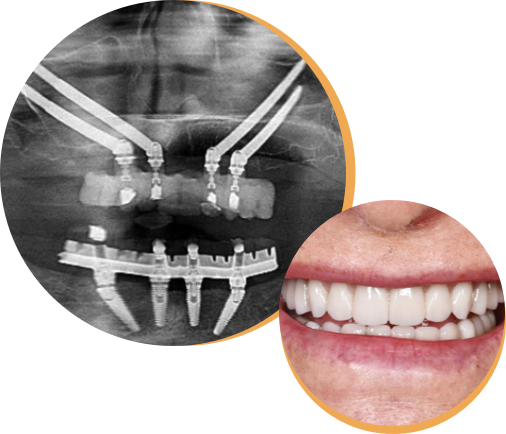

Full dental arch rehabilitation (All-on-4) is an advanced, technically innovative procedure where a fixed bridge is supported by just four dental implants placed in the jawbone.

With the use of zygomatic implants, even in the most extreme cases, it is now possible to rehabilitate the mouth and return to having permanent teeth via dental implants. Zygomatic implants involve securing the bridge to the cheekbone rather than the jaw bone. This avoids the need to rely on bone grafting which can require multiple procedures and lengthened treatment times.